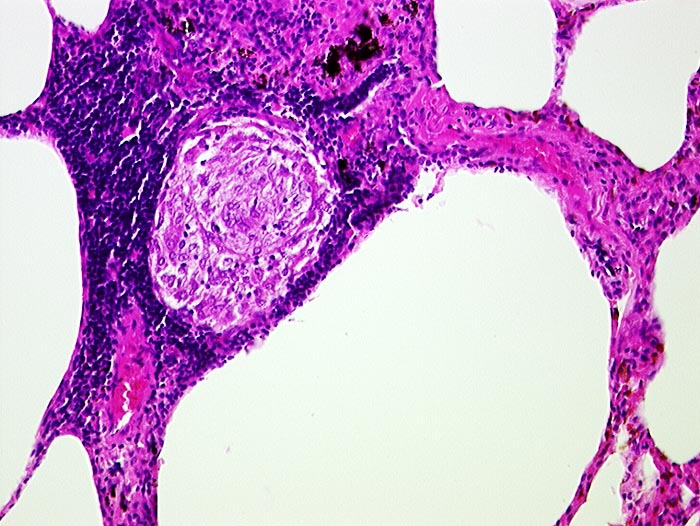

Sarkoidosegranulom

Entzündung / Reparatur

Lunge

Granulom aus Epitheloidzellen umgeben von Lymphozyten in einem Alveolarseptum.

Granulome in Lungen, Bronchialschleimhaut, Leber, Milz und Lymphknoten pulmonal

Histologie